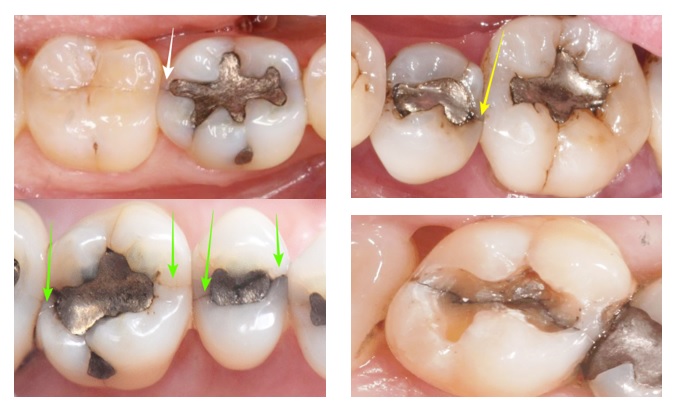

3. 금 인레이, 아말감 등 과거 치료로 인한 문제

금이나 아말감은 금속이죠. 금이나 아말감을 치아에 붙일 때, 단단하게 결합시키는 게 아니라 끼워 넣는 방식으로 붙입니다.

​그리고 금이나 아말감은 금속이라서 강한 힘이 가해지면 치아를 벌리는 힘이 작용됩니다.​

그래서 과거에 금이나 아말감으로 치료한 치아들을 보면 크랙이 있는 경우가 많아요.

​상단 사진은 아말감 주변에 하단 사진은 금 인레이 주변에 크랙이 생긴 경우입니다.